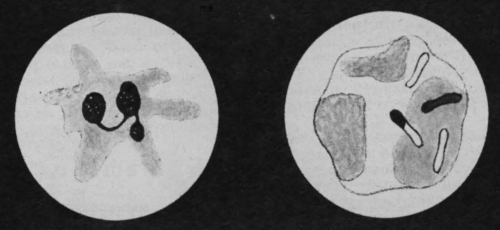

Лейкоцит с псевдоподиями. Фагоцит уничтожает бациллы сибирской язвы

Перемещаются лейкоциты с помощью ложноножек — псевдоподий. В одном из участков клетки появляется выступ, куда переходит часть протоплазмы, затем еще несколько таких же выступов. У клетки образовались ложные ножки.

С их помощью она, правда, очень медленно, может переползать с места на место. Недаром лейкоцит иногда называют блуждающей клеткой или пешеходом.